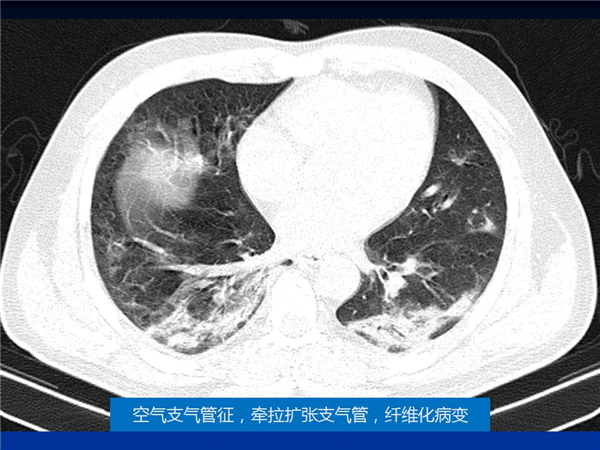

【病例分享】新型冠状病毒感染肺部CT影像4例(常德市第一人民医院)